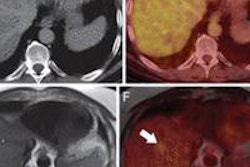

Another new technology, GE's deviceless 4D, eliminates the need for an external device when creating motion-compensated 4D CT scans. The technology offers high-quality images and workflow efficiency in 4D motion assessment for thoracic and abdominal tumors affected by respiratory motion, the company said. It is pending U.S. Food and Drug Administration (FDA) 510(k) clearance.